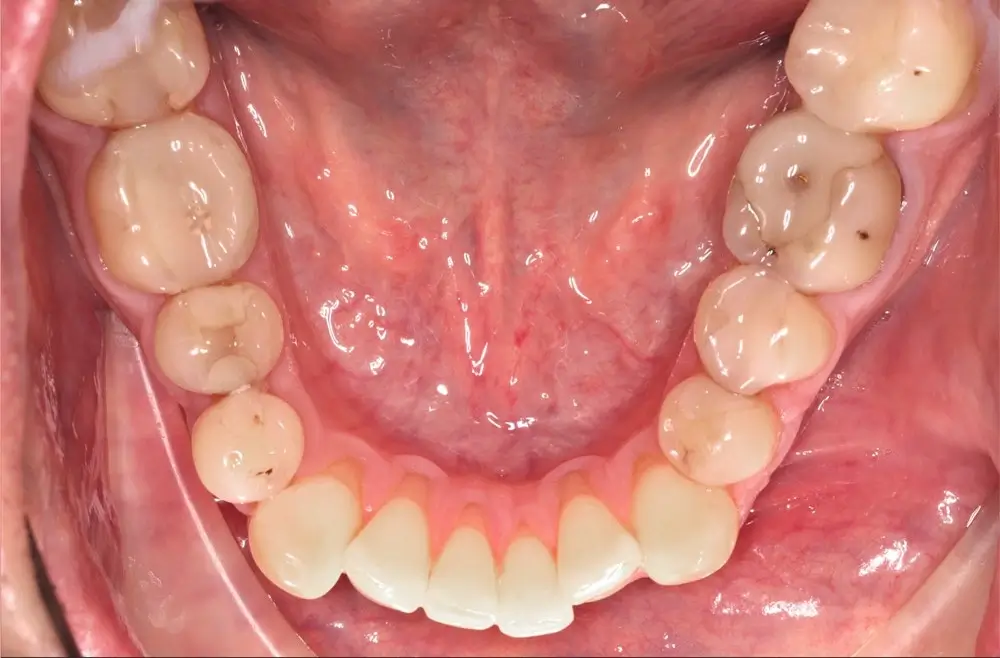

Мезиальный прикус - Кейс 7

Эффективность устранения дефекта прикуса посредством элайнеров FlexiLigner.

Результаты лечения